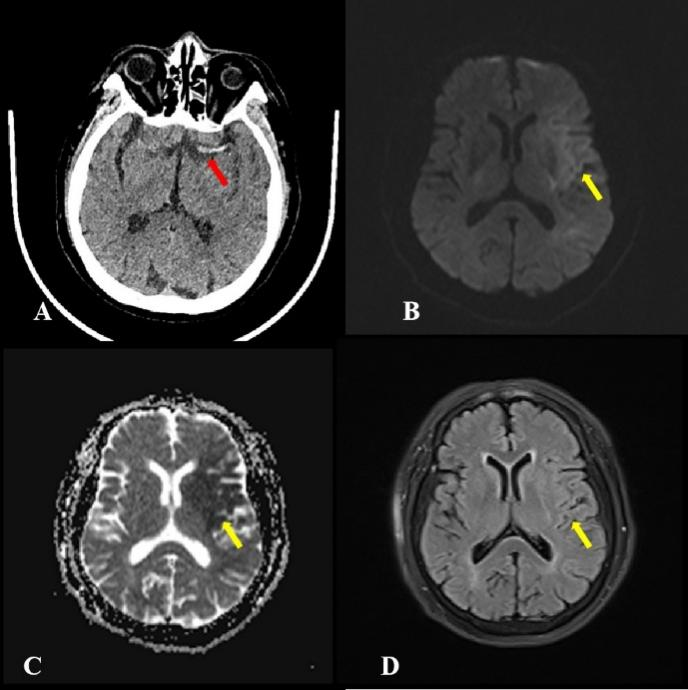

近日,首都医科大学附属北京中医医院急诊接诊一例72岁女性患者,主因睡醒后“意识不清伴右侧肢体偏瘫、失语1小时”入院。美国国立卫生研究院卒中量表(NIHSS)评分19分,既往有房颤史,发病时间不明。患者入院后迅速启动急诊诊疗流程,短时间内完成急诊头颅CT检查。放射科邹锦莉住院医师和李俊秋主任医师阅片时结合人工智能(AI),敏锐地捕捉到一个关键征象:左侧大脑中动脉致密征(图1A),该征象作为大动脉急性闭塞的早期直接征象,为快速锁定病因、提示血栓形成提供了重要线索。基于该初步判断,为进一步明确梗死范围与分期,患者进一步行头颅MRI检查,显示:左侧大脑中动脉供血区可见斑片状弥散加权成像(DWI)高信号(图1 B),对应区域表观弥散系数(ADC)图呈明显低信号(图1C),液体衰减反转恢复序列(FLAIR)(图1D)相应区域未见明显异常信号,即存在DWI-FLAIR不匹配征象。根据当前国内外卒中指南,该影像特征提示脑梗死处于超急性期(发病<4.5小时),支持患者仍处于溶栓时间窗。我院临床团队依据影像评估结果,最终对患者实施了静脉溶栓治疗,患者症状得到改善,后续转入针灸诊疗中心接受治疗,两周后好转出院。

图1(A-D)头CT平扫及MR检查

本案例放射科通过CT与MRI的连续影像评估,先是在CT平扫中早期识别大脑中动脉致密征,并建议进一步检查,再通过MRI捕捉到DWI-FLAIR不匹配的关键征象,为发病时间不明的急性卒中提供了梗死处于超急性期的客观依据,辅助临床在有效的时间窗内及时启动溶栓治疗,提升溶栓治疗的适用性与安全性。这充分体现了放射科在急性卒中多学科协作中,以精准影像信息为临床决策提供支持,助力优化患者救治流程的重要作用。